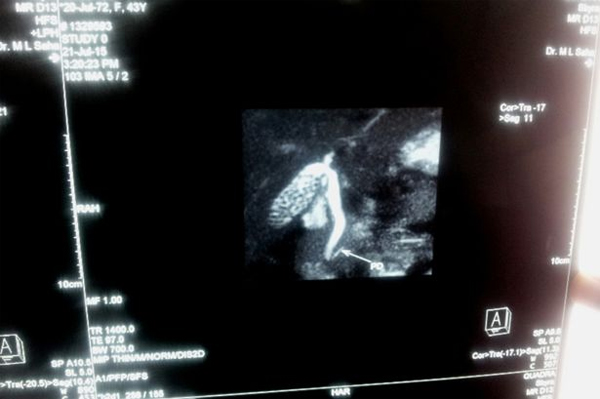

Hình siêu âm cho thấy bọc sỏi trong túi mật của bệnh nhân.

Bác sĩ làm các xét nghiệm và siêu âm sau đó phát hiện ra bà bị sỏi mật nặng, nhưng điều khiến các bác sĩ càng bất ngờ hơn khi phát hiện có đến 360 viên sỏi nằm trong túi mật của bà Dam.

Mỗi viên sỏi có kích thước khoảng 5mm và phải mất gần một giờ đồng hồ để bác sĩ có thể loại bỏ toàn bộ số sỏi trong túi mật của bà Dam. Thật đáng ngạc nhiên là cả 360 viên sỏi đều có cùng kích thước và hình dạng.